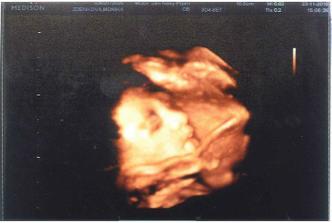

14:10.Poradna,vše je v pořádku dr.udělala u rychlý usg tak se tam zrovna mimčo modlilo a bylo moc spokojené.Za měsíc mám +2kg